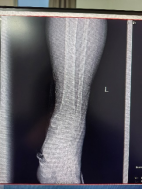

患者56歲男性,外傷致左踝部疼痛出血、腫脹畸形、活動受限,X線片顯示左脛腓骨遠端碎折,骨折斷端嵌插,骨折波及關(guān)節(jié)面,左脛骨近端內(nèi)側(cè)骨質(zhì)連續(xù)性中斷。

患者先于2025.2.15行左脛骨平臺骨折切開復位內(nèi)固定術(shù)。

于2025.2.21行三臂機器人輔助下脛骨遠端骨折切開復位內(nèi)固定術(shù)。